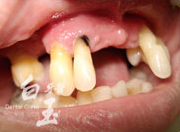

治療前